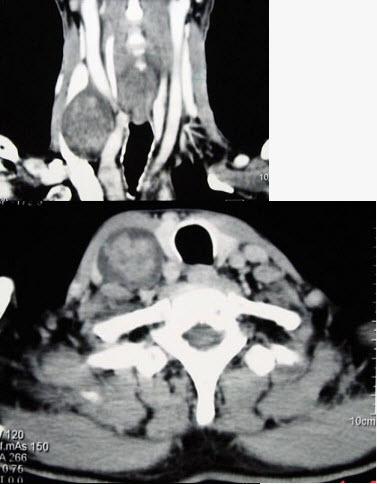

男性,70岁,右侧颈部无痛性肿块3个月,CT扫描如图所示,请选择正确的描述和答案()。

A . 右颈动脉间隙内见类圆形软组织肿块影,密度欠均匀,边缘光整

B . 右侧颈静脉被推压至肿块外后方

C . 右侧颈动脉被推压至肿块内后方

D . 考虑迷走神经源性肿瘤

E . 考虑交感神经源性肿瘤